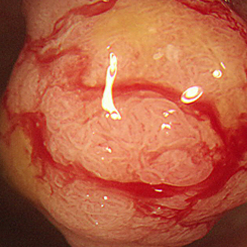

| 위내시경 검사 | 위내시경은 내시경을 이용해 식도, 위, 십이지장의 점막을 직접 관찰하여 염증, 궤양, 종양 등의 이상 여부를 확인하는 검사입니다. 조기위암 병변은 육안상 염증과 구분이 어려워, 의심 병변에서 조직을 채취해 병리학적으로 확인하는 조직병리검사를 할 수 있습니다. 또한 헬리코박터균은 위암 발생 위험을 높이는 요인으로, 감염이 의심될 경우 검체를 채취해 헬리코박터균 유무 를 확인할 수 있습니다. |